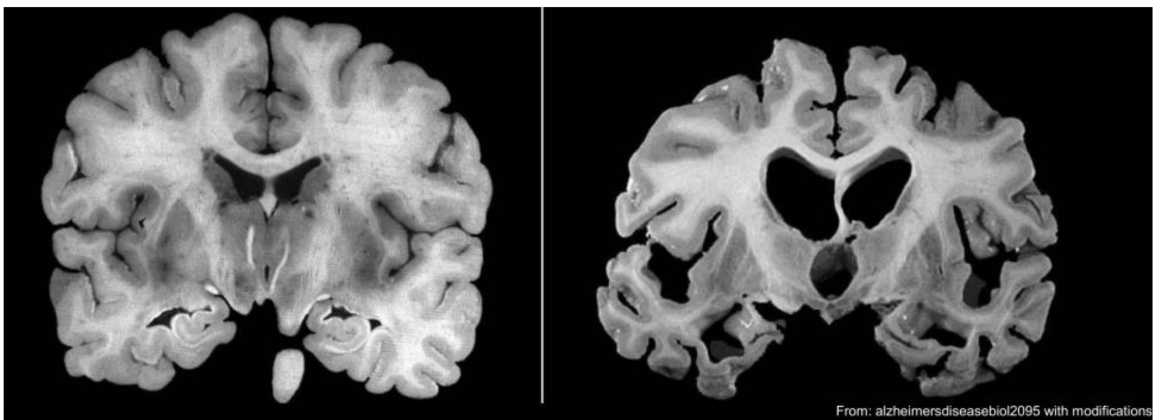

Welcome to the Norwegian National anti-Alzheimer’s disease network (NO-AD): A Norway-anchored international research network dedicated on communication and collaborations for better and faster mechanistic studies, biomarker development, new drug discovery, care, and intervention of Alzheimer´s disease. We are actively organizing seminars on ageing and Alzheimer´s disease, see the forthcoming/past talks ´Meetings´ and past recorded talks ´Videos´.